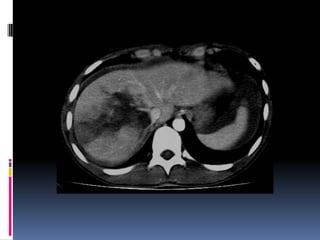

¿LÍQUIDO LIBRE HIPERDENSO? Diagnóstico: RUPTURA VESICAL